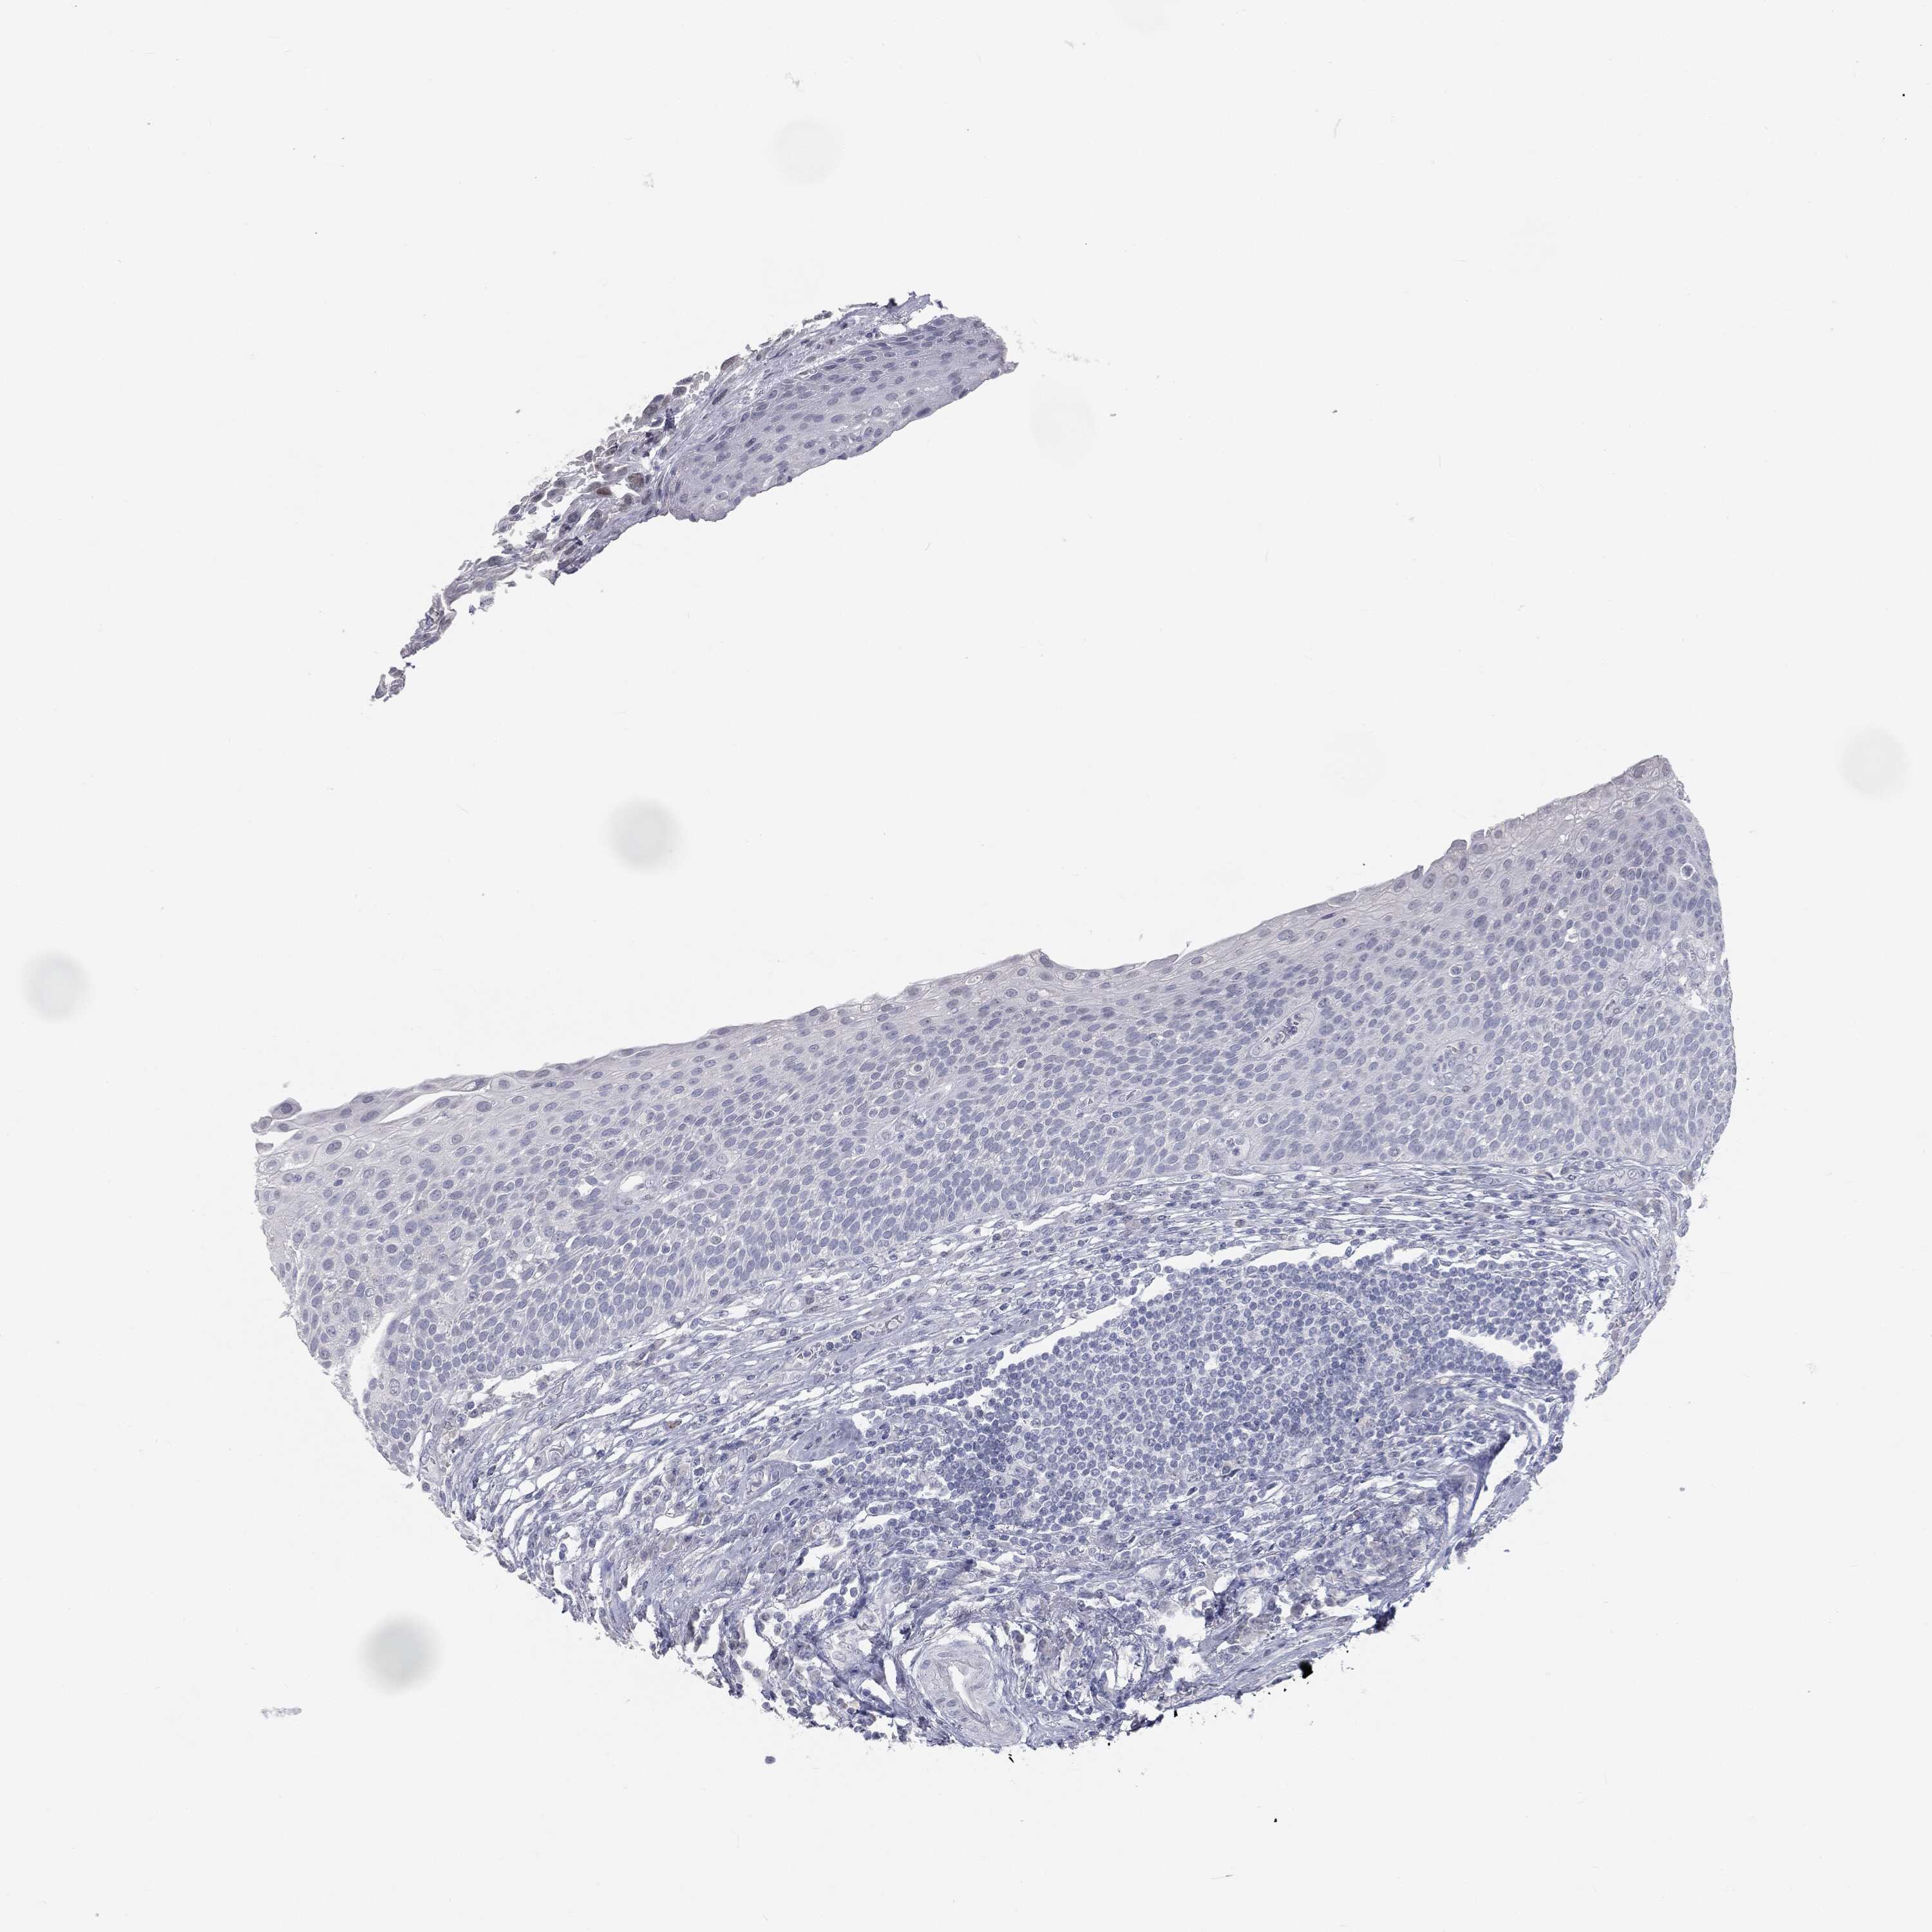

UROTHELIAL CANCER - Protein expressioni

A mouse-over function shows sample information and annotation data. Click on an image to view it in a full screen mode. Samples can be filtered based on level of antibody staining by selecting one or several of the following categories: high, medium, low and not detected. The assay and annotation is described here.

Antibody stainingi

Antibody staining in the annotated cell types in the current human tissue is reported as not detected, low, medium, or high, based on conventional immunohistochemistry profiling in selected tissues. This score is based on the combination of the staining intensity and fraction of stained cells.

Each image is clickable and will lead to virtual microscopy that enables deeper exploration of all samples and also displays staining intensity scores, fraction scores and subcellular localization as well as patient and tissue information for each sample.

Antibody HPA045153

Antibody CAB080138

Urothelial carcinoma, High grade

Urothelial carcinoma, NOS

Urothelial carcinoma, Low grade